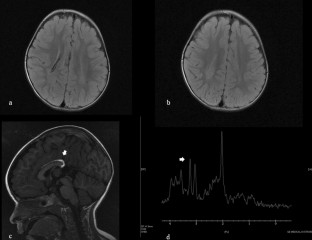

Losito, L., Gennaro, L., Lucarelli, E. et al. Brain MRI abnormalities in a child with spinal muscular atrophy type II. Acta Neurol Belg 121, 1883–1885 (2021). https://doi.org/10.1007/s13760-020-01524-x